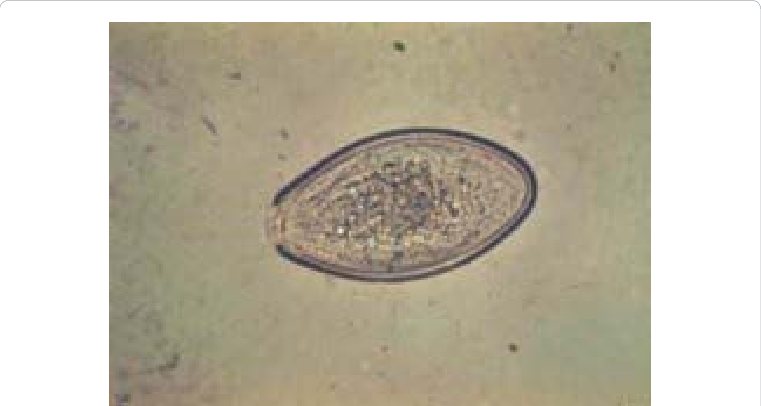

Trichuris vulpis

Host: T. vulpis-canine, T. campanula- and serrate-feline; Common name: whipworm; *feline whipworms are rare; Clinical signs: diarrhea, anemia, mucus covered stool; Diagnoosis: fecal flotation; Treatment: Mebendazole, fenbendazole; or ivermectine